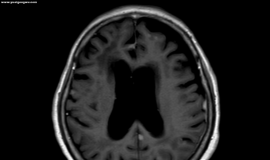

脑膜转移:隐秘而凶险的终极并发症

上厕所晕倒,很有可能是脑部有问题,如果没有加强核磁可见的病灶和异常,可以继续观察看是否还有其他神经系统症状,如步态不稳,失语,视觉和味觉改变等。如果逐步发现上述症状,要做好脑膜转移的准备。